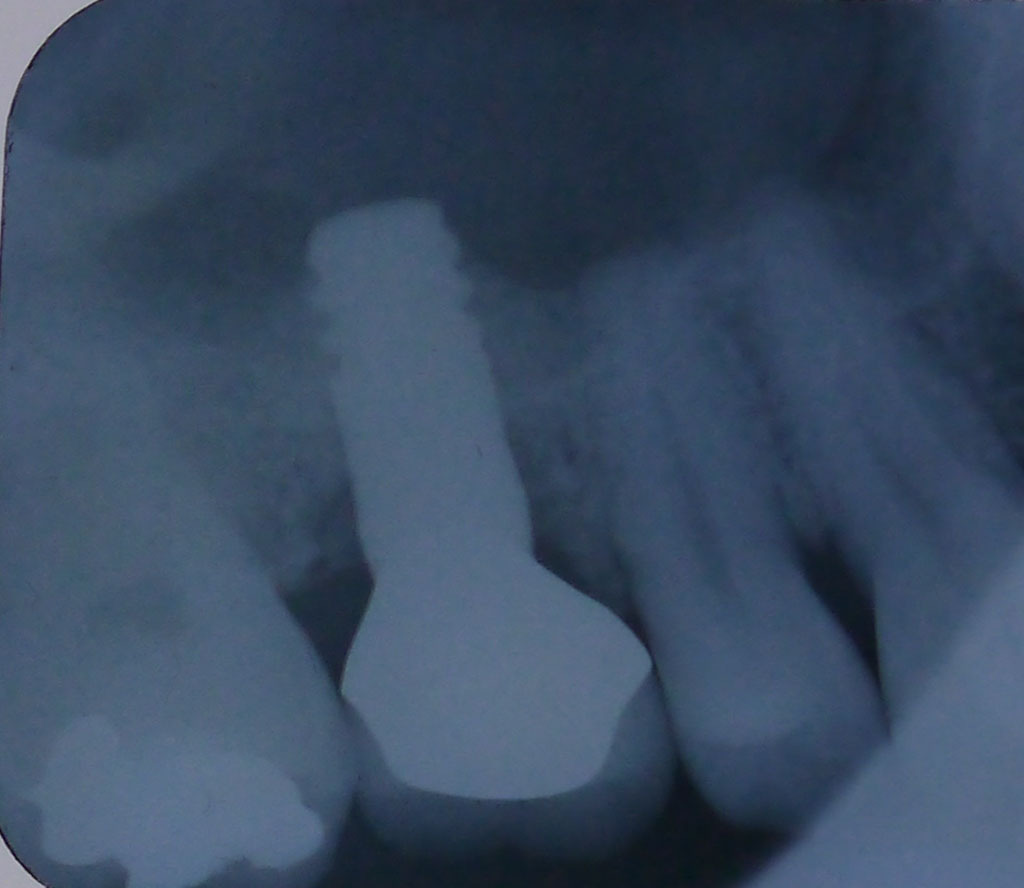

レントゲン画像2

平成24年8月17日、4ヶ月半後のレントゲン画像 だいぶ骨が出来ている